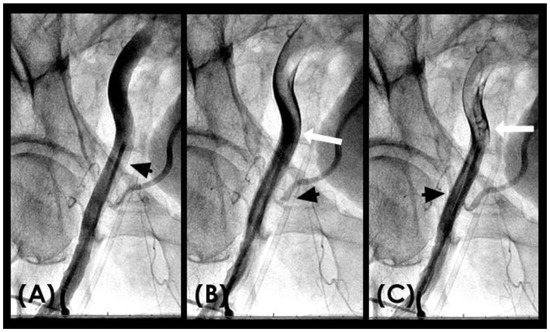

RETROGRADE contrast flow: In this iliac angiogram recorded by the novel dynamic angiographic technique, near the end of systole and in the first half of diastole, the retrograde flow is observed as a black contrast moving upwards from the iliac arteries towards the aortic bifurcation (Figure 6A–D). In contrast, for the right coronary artery (RCA), the retrograde flow happened mainly in the first half of systole. The retrograde flow in the coronary artery will be discussed in more detail in the next section.

Figure 6.

(A–D) Retrograde flow in the iliac artery. These are consecutive images separated from each other by 0.067 s. (A) Near the end of systole, the contrast (in black) could be seen moving upwards with a blunted, curved head (arrow). (B–D) In each image, separated by 0.67 s, the column of contrast was seen mixed with white-colored blood moving further up with a blunted, curved head (arrow).